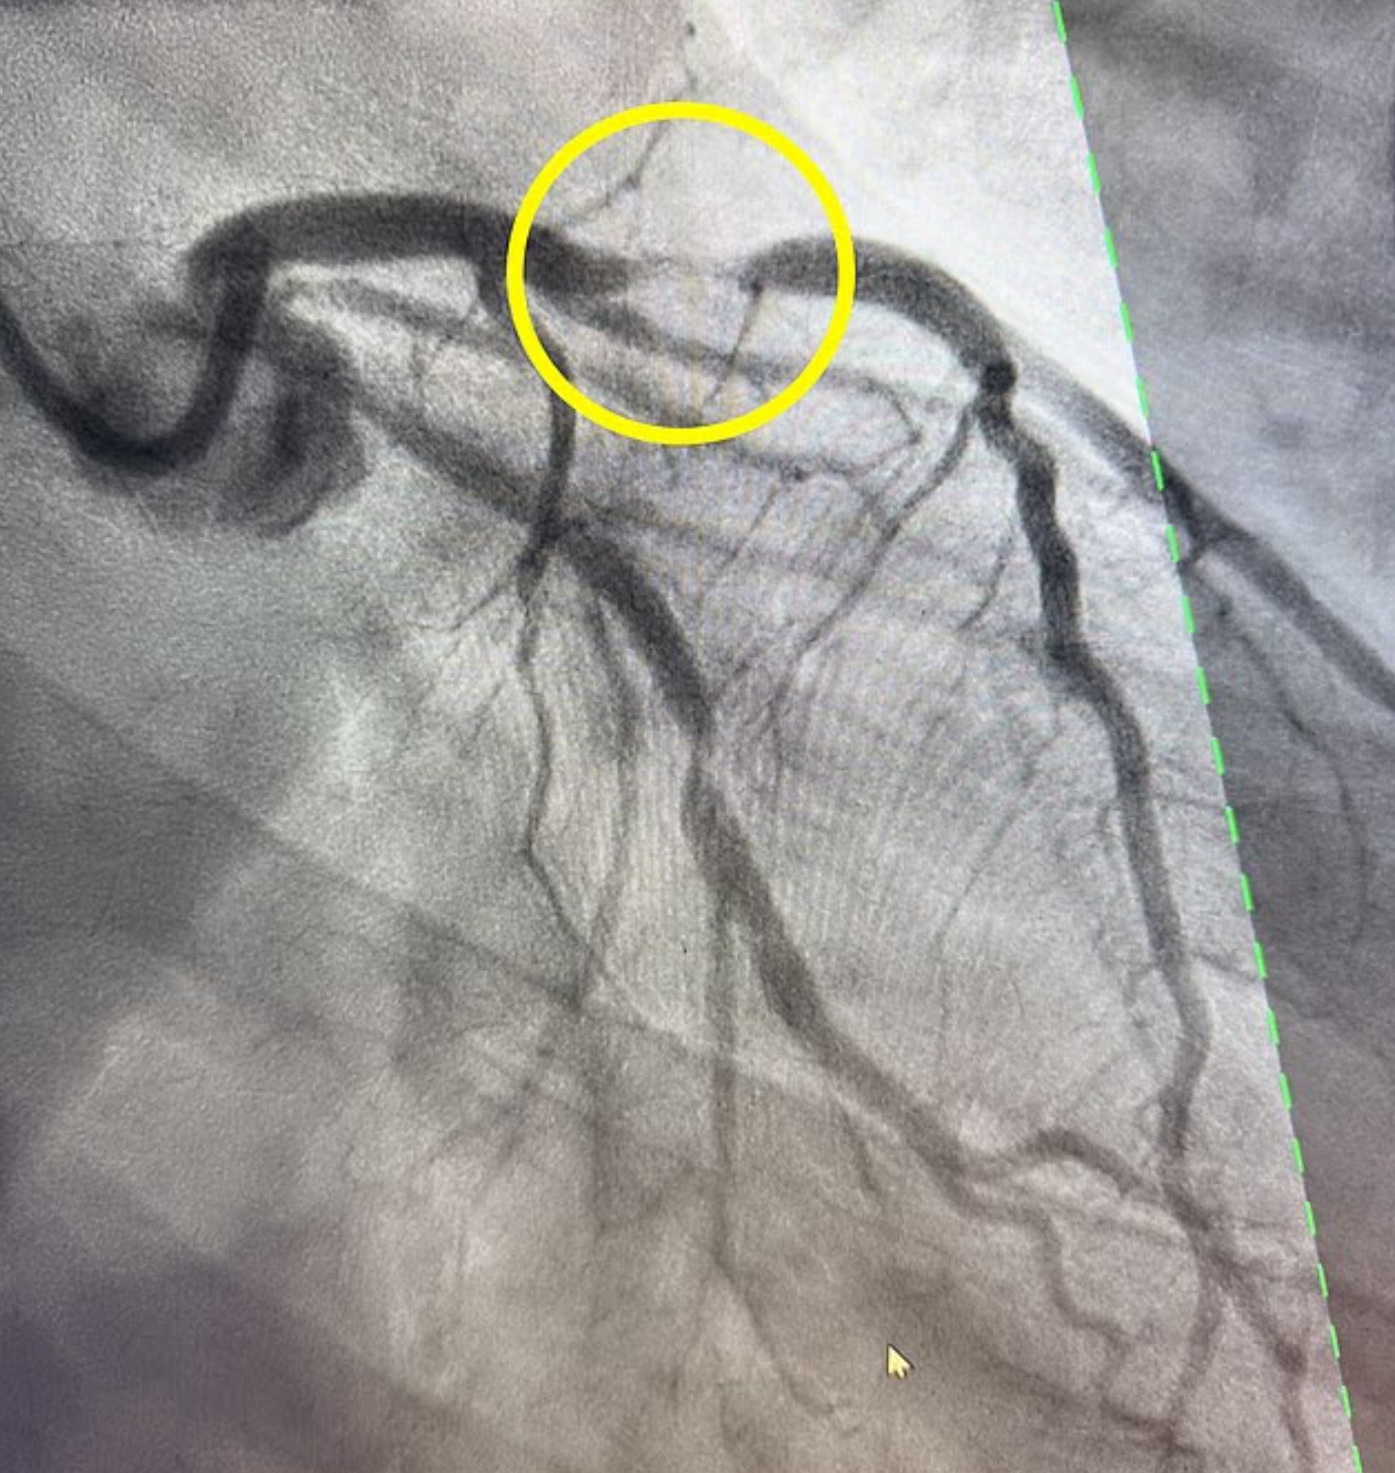

Mario認為可能出現心臟病發作的症狀,遂立即趕往醫院,醫生發現他的左前降支動脈血管阻塞了95%,恐導致心臟病發作,死亡率極高,醫生估計只有12%的患者能夠存活,因阻塞左前降支動脈會立即對心臟的泵血腔室造成巨大損害。這種心臟病在男性中更常見,尤其在40多歲的男性中,但50歲以上的女性風險也會增加。